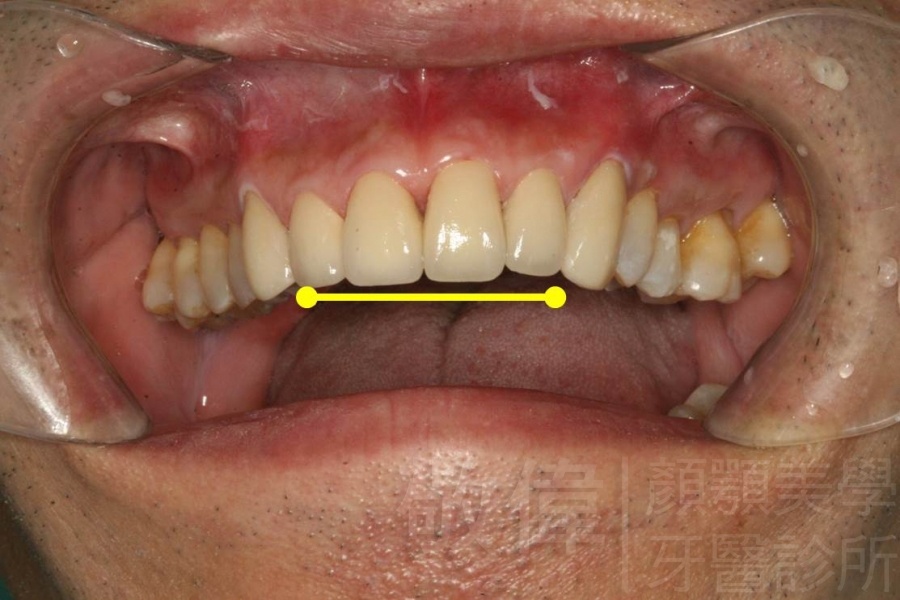

| 6 | 前牙美容 | 矯正+牙齦增補+晶鑽全瓷冠 | ||

| 7 | 前牙美容 | 矯正+晶鑽全瓷冠 | ||